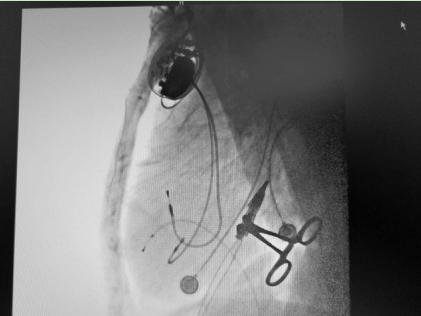

起搏器成功植入

3天后成功植入心臟永久起搏器——熬過了前面的生死難關(guān),3天后,朱彬為老人實施了雙腔心臟永久起搏器植入術(shù),并程控相關(guān)參數(shù)以滿足患者個體狀態(tài)所需,手術(shù)過程順利,疾病得到根治。7天后,老人康復(fù)出院,出院后長期門診隨訪未再出現(xiàn)暈厥,生活能夠自理。